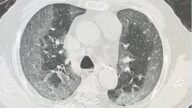

雖然中共極力掩蓋疫情,但感染人數激增,重症和死亡病例大量湧現,特別是不少患者出現了「白肺」現象,與奧密克戎感染上呼吸道的情況不符。而中共衛健委的闢謠,則是加深了人們的相關猜測。

中共國家衛健委醫政司司長焦雅輝:「現在出現的這個所謂的『白肺』,與武漢當時的原始毒株,和疫苗接種是沒有關係的,並且當前的流行優勢毒株,仍然是奧密克戎毒株。」